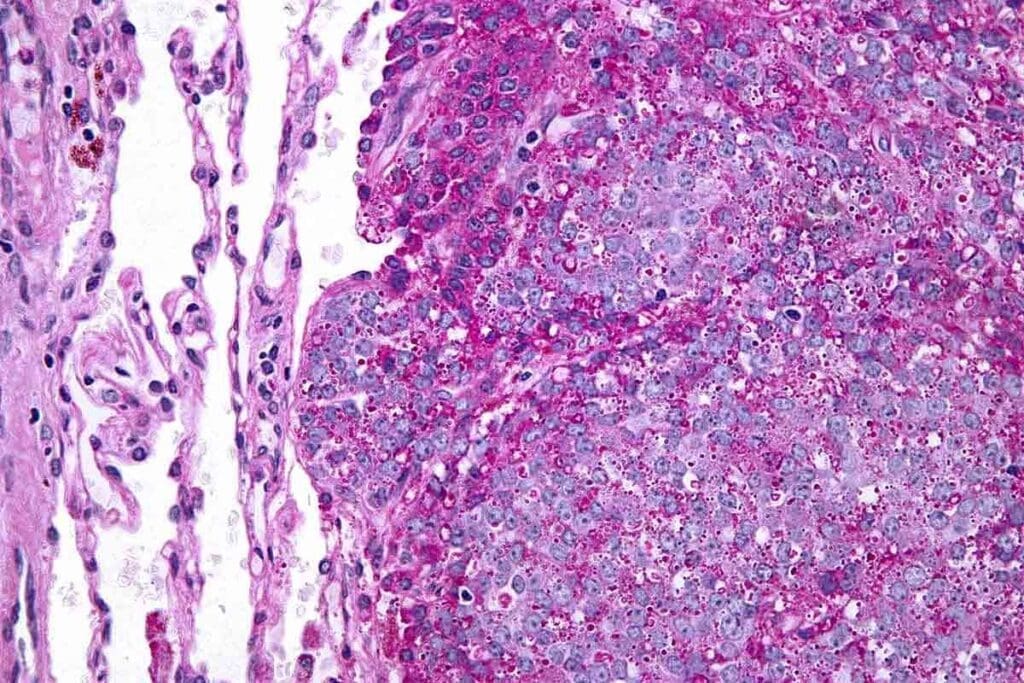

Diagnostic Approaches and Staging

Diagnosing Ewing sarcoma involves imaging studies, biopsy, and genetic analysis. X-rays, CT scans, MRI, and PET scans help see the tumor’s size and location. A biopsy confirms the diagnosis through histological examination and genetic testing.